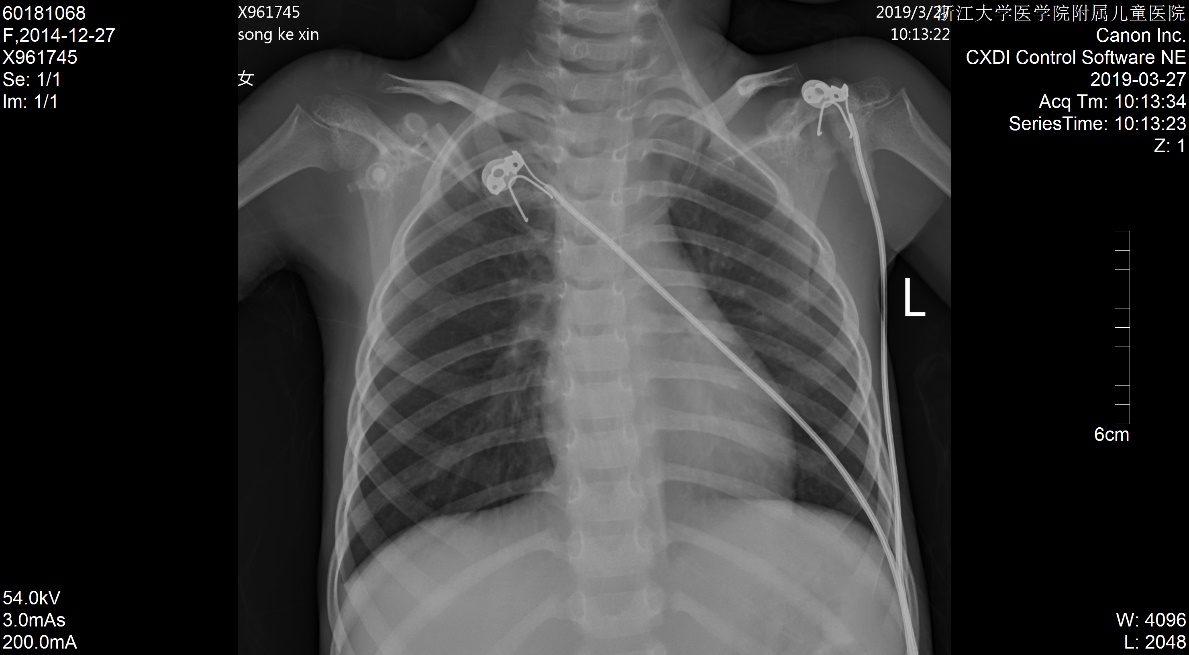

1 资料与方法患儿女,5岁2月,因“多尿、多饮、多食3个月余,意识不清1天余”由外院转入。3个月余前出现多尿、多饮、多食,家长未重视,未就诊。1 d前出现意识不清,并抽搐3次,急送当地医院就诊,当时查体情况具体不详,查血气电解质示pH 6.87,pCO225.9 mmHg,Na+ 125.4 mmol/L, Glu 17.1 mmol/L,Lac 1.1 mmol/L,HCO3- 4.6 mmol/L,ABE -28.1 mmol/L。考虑诊断“糖尿病、糖尿病酮症酸中毒、脑水肿?”收住当地医院。在当地医院住院期间,予大量补液[约3 L/24 h,大部分为晶体液,可能因为低血压,因住院期间曾使用多巴胺10 μg/(kg·min)维持],住院期间出现氧饱和度不能维持,遂予气管插管并机械辅助通气。因病情持续恶化,联系后转入本院PICU。既往史、个人史、出生史无殊。爷爷及外婆有糖尿病及高血压病。入院查体:T 37.8℃,脉搏:146次/min,呼吸:38次/min(为机械通气),血压98/77 mmHg(1 mmHg=0.133 kPa),无特殊面容及畸形,体质量:11 kg,气管插管带入,经皮血氧饱和度95%,镇静状态,双侧瞳孔等大等圆,直径2 mm,对光反射存在,颈软,余神经系统无明显阳性体征,面色苍白,消瘦貌,双肺呼吸音粗,可闻及湿啰音,腹软,肝脾肋下未及,皮肤弹性略差,肢端凉,毛细血管充盈时间5 s。入院后查白细胞计数8.52×109/ L-1,淋巴细胞15.4%,中性粒细胞82.0%,超敏C反应蛋白17.33 mg/L;血气分析:pH 6.996,pO2 91 mmHg, pCO2 43.5 mmHg,Na+ 126 mmol/L,Glu 21.0 mmol/L,Lac 2.9 mmol/ L,HCO3- 10.1 mmol/L,ABE -20.6 mmol/L;血氨63 μmol/ L;生化五类:总蛋白34.9 g/L,白蛋白26.5 g/L,丙氨酸氨基转移酶24 U/L,天门冬氨酸氨基转移酶96 U/L,肌酐147 μmol/L,尿素12.38 mmol/L,肌酸激酶1 680 U/L,肌酸激酶-MB活性166 U/L,甘油三酯6.05 mmol/L,胆固醇6.11 mmol/L,淀粉酶3 094.5 U/L;尿常规:尿酮体++,尿蛋白++,尿糖++++,尿隐血+++;糖化血红蛋白16.5%;血清C肽测定:0.116 nmol/L;糖尿病自身抗体阳性;脑脊液常规、生化及培养无殊;血尿培养阴性;胸片:两肺弥漫性病变,双侧胸腔积液,肺水肿待排(图 1);心超:左室收缩功能稍减低(EF 0.53),少量心包积液,二、三尖瓣轻度反流;腹部B超:肝大、腹腔积液。考虑诊断“急性呼吸窘迫综合征、急性肾功能损伤、1型糖尿病、糖尿病酮症酸中毒、脑水肿、多浆膜腔积液”,予呼吸机支持[HFO模式,FiO2:85%,f:5.8 HZ,ΔP:36 cmH2O(1 cmH2O=0.1 kPa),MAP:25 cmH2O, OI:23)、多巴胺及肾上腺素泵注维持血压、甘露醇降颅压、胰岛素注射降血糖及其他对症支持治疗,患儿入院第3天酮症酸中毒基本纠正,第6天改无创通气(CPAP,Flow:10 L/min,PEEP:4 cmH2O),入院第10天改大气吸入,复查胸片基本好转(图 2),住院期间未再抽搐,在停呼吸机机械通气镇静后意识好转,但较激惹、躁动,肾功能逐步恢复,住院28 d后出院,出院前患儿意识清,能完成日常对答,查头颅MRI提示脑萎缩改变,复查肺部影像学未出现遗留性病变,复查心超未见心包积液。现规律随访近一年,胰岛素治疗血糖控制尚可,未遗留明显神经系统、呼吸系统等后遗症。本研究经浙江大学医学院附属儿童医院伦理委员会批准(批准号:2020-IRB-078),并经患儿家属知情同意。

| 图 1 入院时胸片 |